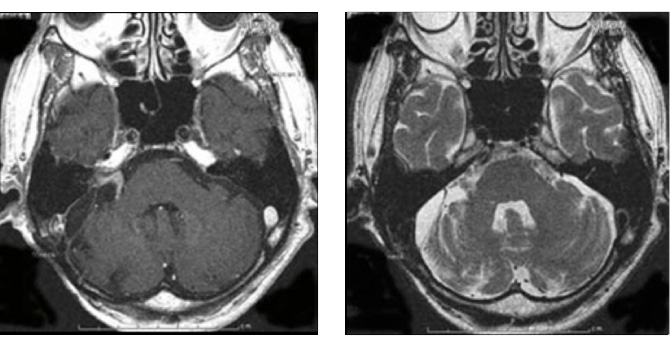

また高齢者でも手術は有益です。図2の症例は80歳の男性症例ですが、10年来右耳難聴で聴神経腫瘍の診断はつけられておりましたが、治療希望せず放置されておりました。しかし歩行障害が進行し当院に紹介されてまいりました。

造影MRIでは大型の腫瘍を認め、周囲の脳幹や小脳が強く圧迫され腫れています。手術にて90%の腫瘍摘出を行い、脳の圧迫もとれ、症状も改善し、治療後3年たった現在でも元気で外来に通っていらっしゃいます。

図2:80歳男性 歩行障害をきたした大型神経鞘種

(左図)治療前MRI:顕著な脳の圧迫と脳浮腫を認める

(左図)術後2年後のMRI:薄い残存腫瘍をみとめるが再増大なく、脳の圧迫は改善している